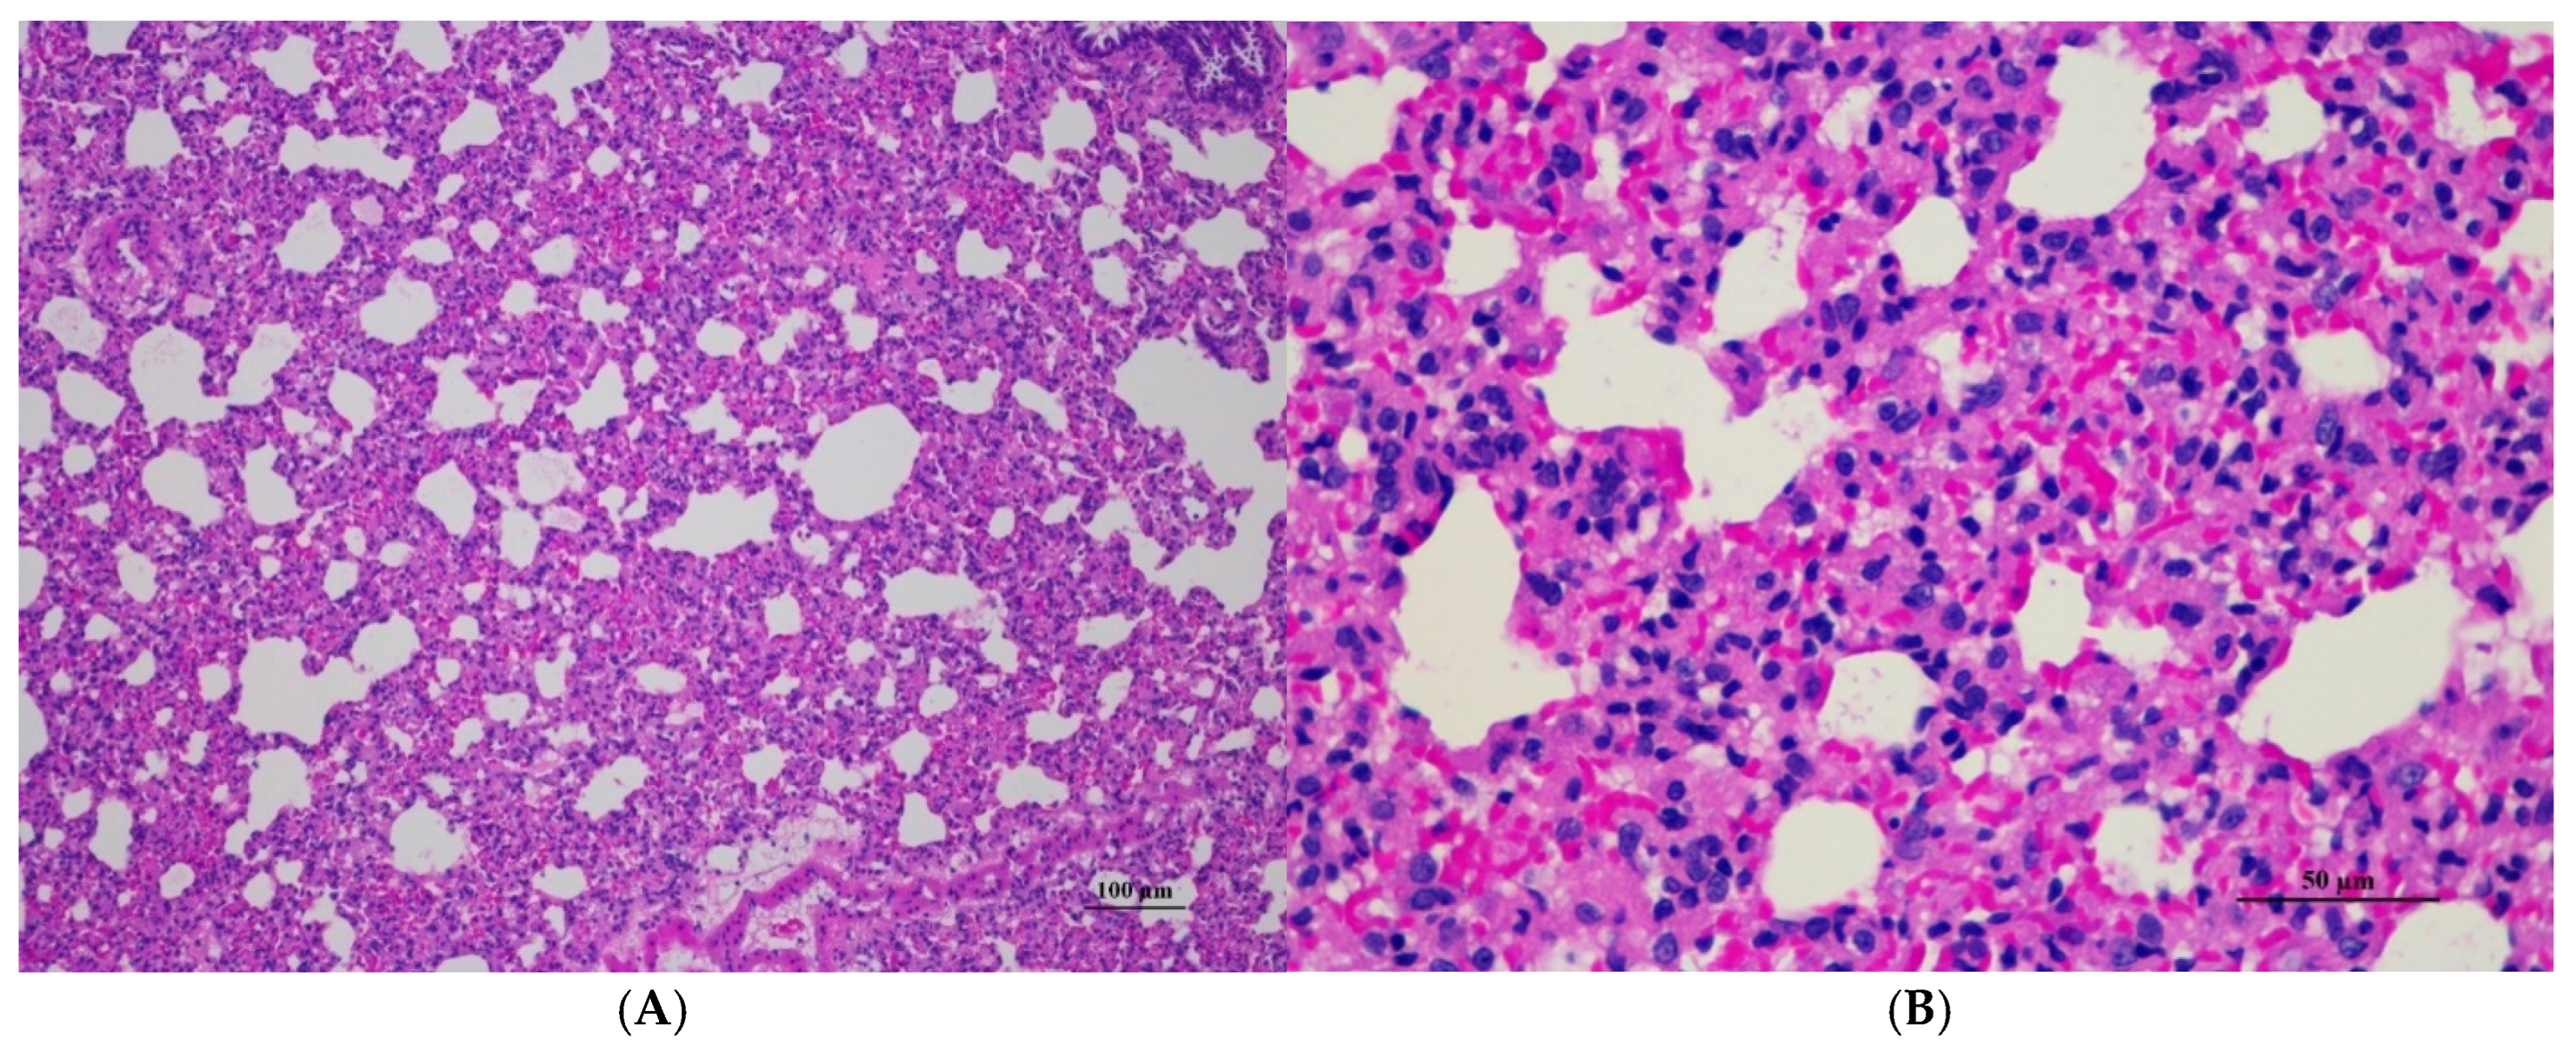

Figure 5.

Histopathological examination of rat lung tissue in acute toxicity from a single oral dose of CDF exhibited histopathological changes. (A) Lung tissue shows marked alveolar septa thickening with disrupted alveolar structure. Interstitial areas are expanded by cellular infiltrates (100×, H&E). (B) High magnification showed septal infiltration by mononuclear cells, hyperemia, and mild hemorrhage in alveolar space (400×, H&E).

Histopathological analysis revealed generally unremarkable findings in the liver, kidney, heart, and spleen, with only minor, scattered hepatocellular swelling and vacuolation in the liver, mild renal tubular degeneration in limited kidney areas, and focal myocardial vacuolation and lymphoid aggregation in the heart. Conversely, the lung exhibited significant pathological changes, characterized by alveolar septal thickening due to severe interstitial infiltration of lymphocytes and other mononuclear cells, nodular lymphoid aggregations, alveolar septal engorgement and hyperemia, alveolar edema, and multifocal mild alveolar hemorrhage, suggesting a potential site of inflammatory response.

Lung abnormalities in the lung tissue of both sexes were found, i.e., interstitial pneumonitis. The histopathologic features of the lungs show varying severity degrees of alveolar edema, alveolar septal engorgement, alveolar hemorrhage, and inflammatory cell infiltration to pulmonary parenchyma. In all groups, this abnormality may indicate infection from laboratory animals. However, further investigation is required. Cassava pulp dietary fiber was found to be well tolerated in a short-term toxicity assessment with non-toxic thresholds of 10.01 g/kg body weight/day for male rats and 11.21 g/kg body weight/day for female rats. Cassava pulp dietary fiber also showed cholesterol-lowering effects [4].